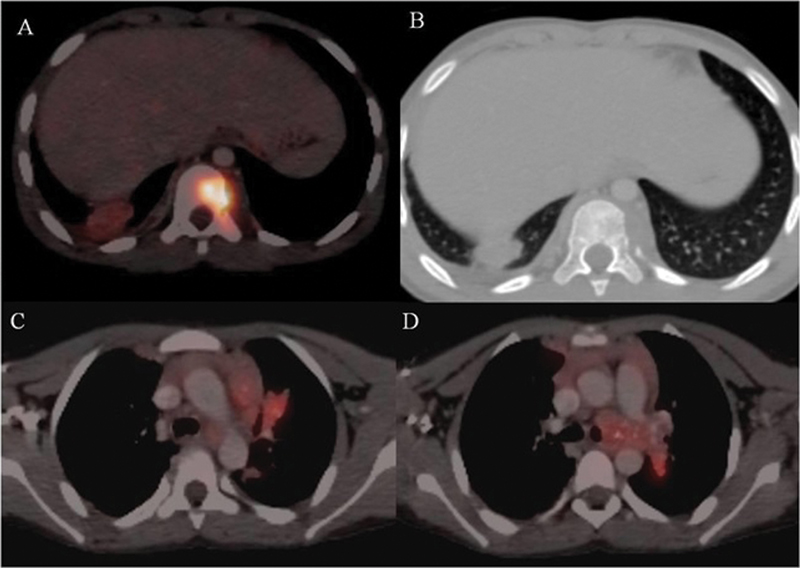

There was no pallor or organomegaly. Positron emission tomography-computed tomography was done outside our institute that revealed a hypermetabolic osteolytic lesion in the frontal bone in the midline as shown in [Fig. 1] and D10 vertebra body associated with soft tissue component. Pleural and parenchymal nodules with associated mediastinal lymph nodes (left hilar, left prevascular, aorta pulmonary, paratracheal, pretracheal and subcarinal nodes) were also seen as shown in [Fig. 2]. A frontal bone lesion biopsy was performed under ultrasonography guidance for further assessment, and the sample was tested for acid-fast bacilli staining and polymerase chain reaction (cartridge based nucleic-acid amplification) testing. Results revealed necrotizing granulomatous inflammation of TB etiology. The patient took antitubercular drugs including rifampicin (10 mg/kg), ethambutol (15 mg/kg), isoniazid (5 mg/kg), and pyrazinamide (25 mg/kg) for a period of 3 months followed by rifampicin (10 mg/kg) and isoniazid (5mg/kg) for the next 9 months. The swelling size reduced and complete resolution of the scalp lesion was noted 3 months post initiating the therapy.

| Fig 1 : (A) Axial computed tomography (CT) soft tissue window shows a lytic lesion in the frontal bone with associated soft tissue (red arrow). (B) Axial CT bone window shows soft tissue in the frontal bone associated with erosion of underlying bone. No periosteal reaction was seen. (C) The fused transverse image shows 18F-fluorodeoxyglucose avid lytic frontal bone lesion. Possibilities on imaging were Langhans cell histiocytosis, metastasis. Frontal bone lesion biopsy revealed necrotizing granulomatous inflammation of tuberculous etiology.

Our case likely belonged to this subtype of tubercular osteitis, based on its radiological features as seen in [Fig. 1].